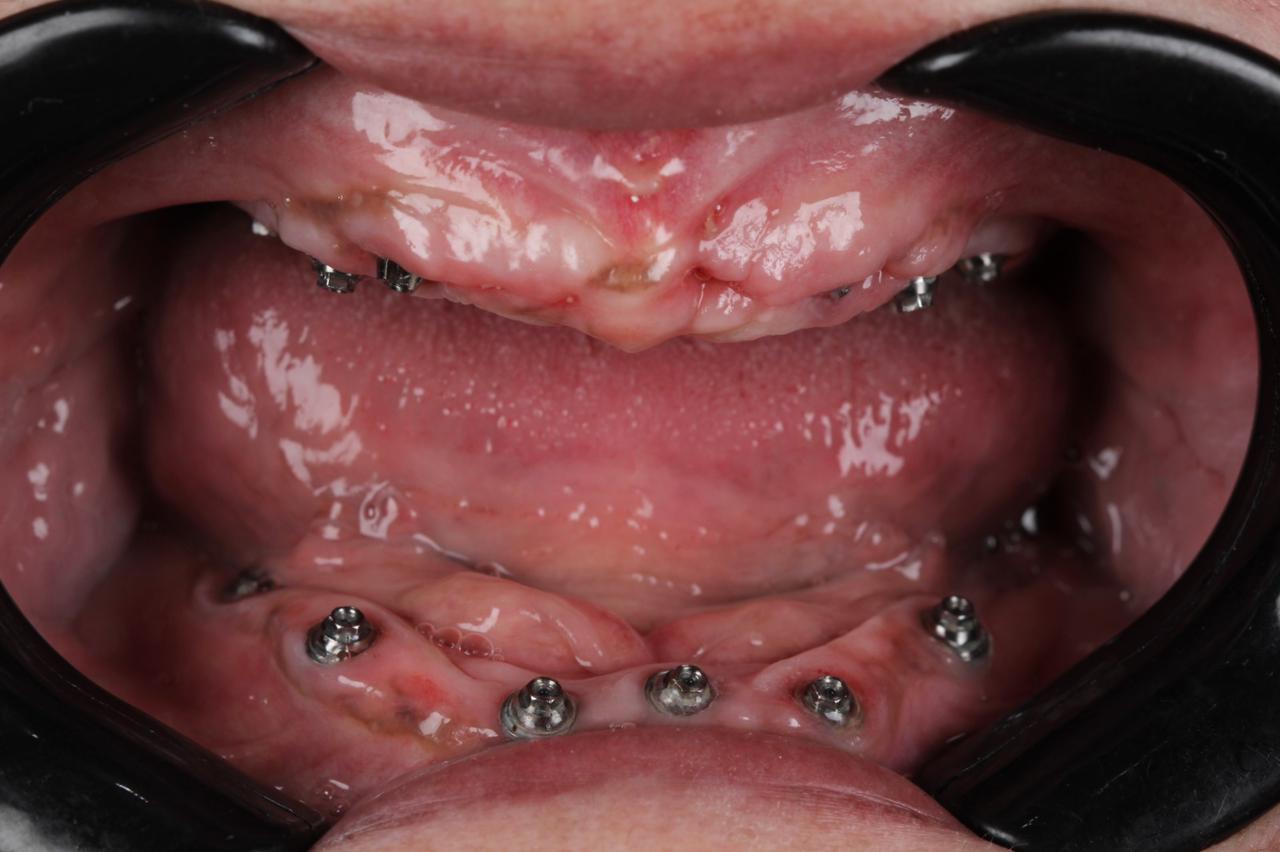

زراعه الأسنان